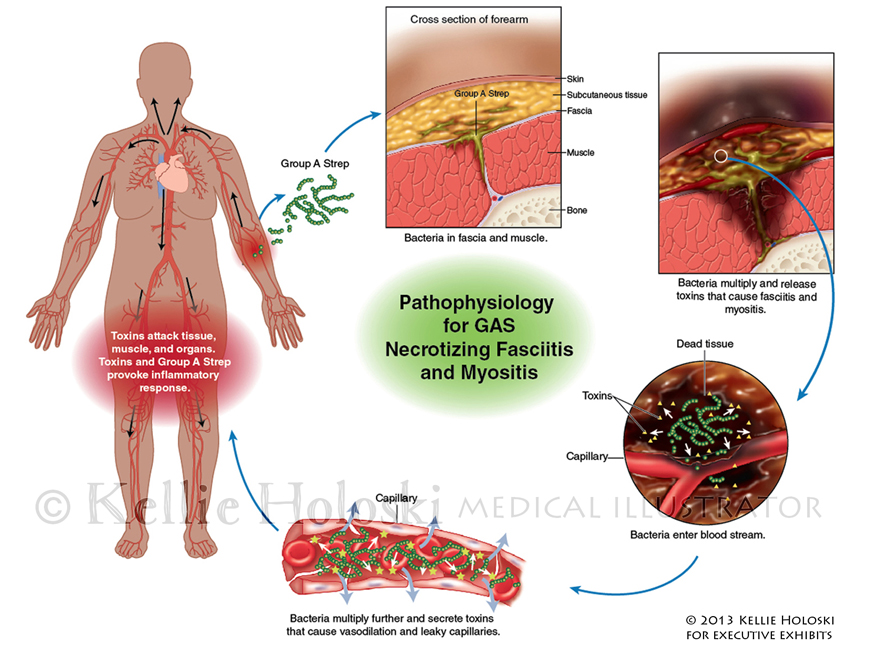

Pathophysiology for GAS,

Adobe Photoshop

Courtroom exhibit for Executive Exhibits;

©Kellie Holoski -